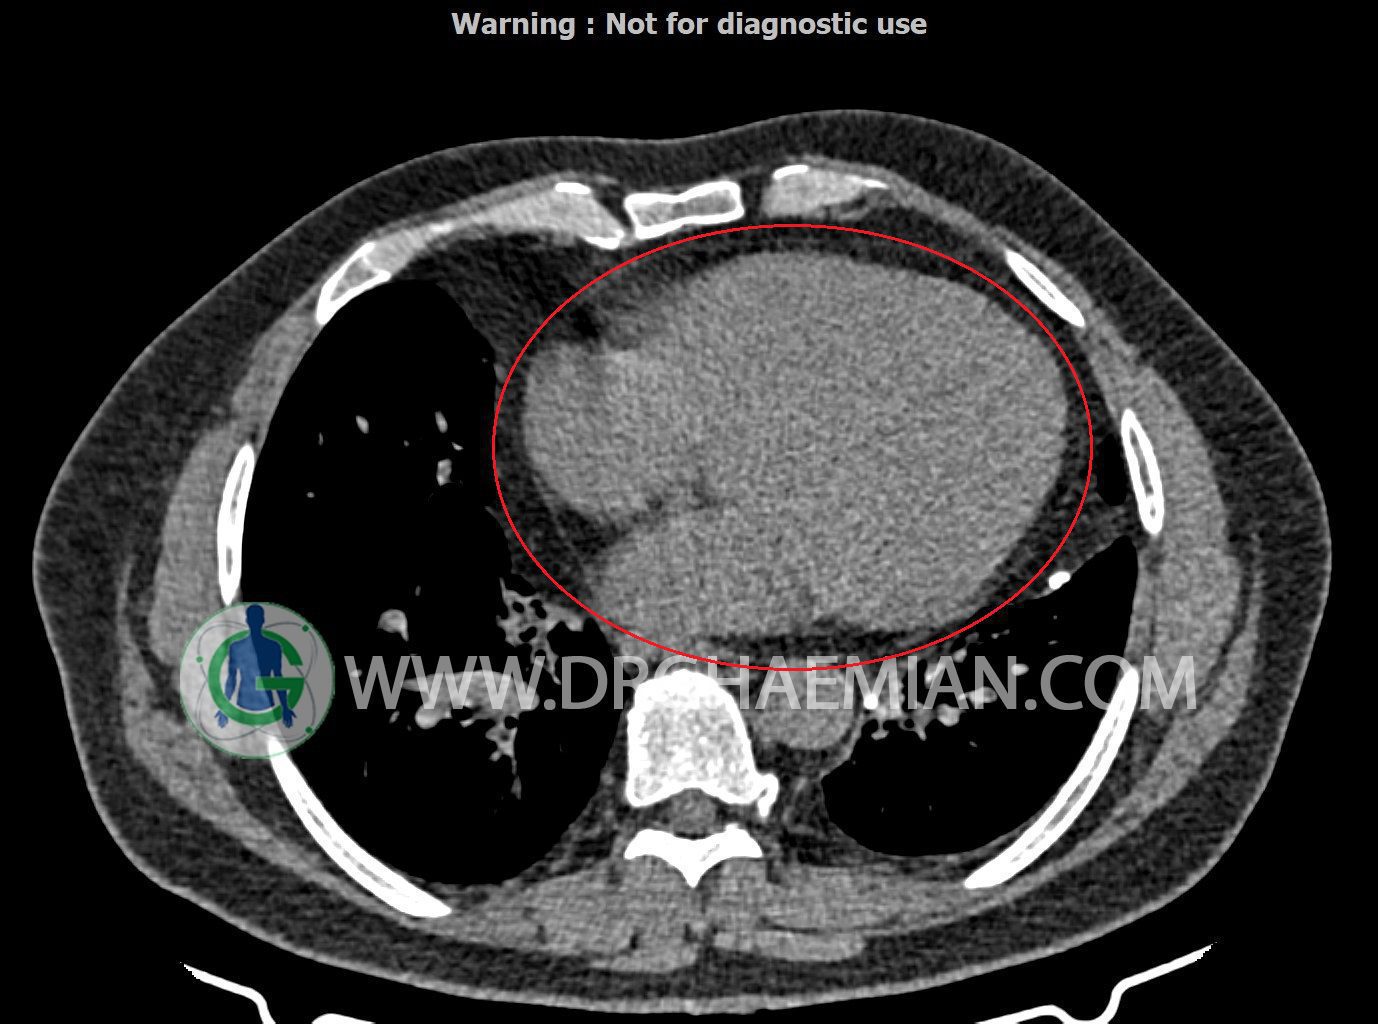

سی تی اسکن ریه یک روش تصویربرداری است که با استفاده از تشعشعات تصاویر عرضی مقطعی از ریه و بالا تنه ایجاد می کند. در این کیس کاردیومگالی،باندهای آتلکتازی و فیبروتیک پراکنده،کدورت های گراند گلاس،زمینه ی ادم قلبی (مراحل اولیه)،مشهده میشود.

کاردیومگالی

شواهد فوق در درجه اول می تواند در زمینه ی ادم قلبی (مراحل اولیه) باشد.